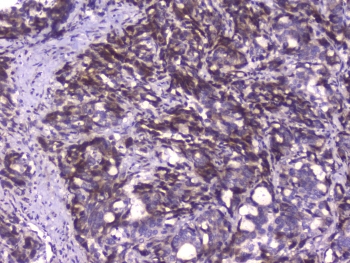

IHC staining of FFPE human stomach cancer with Capicua antibody at 1ug/ml. HIER: boil tissue sections in pH6, 10mM citrate buffer, for 10-20 min followed by cooling at RT for 20 min.